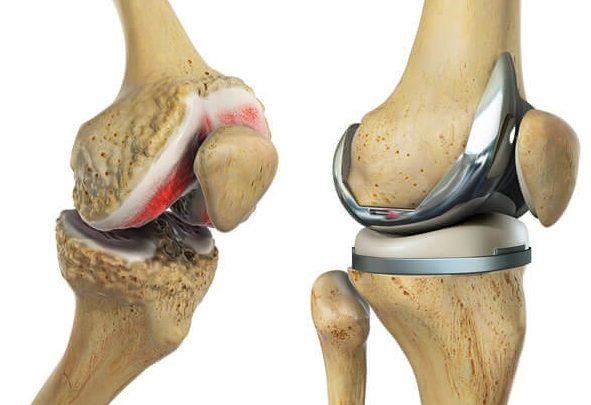

El que se usa de manera normal con excelentes resultados a largo plazo es la prótesis total de rodilla. Las prótesis de rodilla cementada consisten de tres implantes fijados al hueso con cemento: una arriba en el fémur (muy liso y hecho frecuentemente de Cobalto Cromo), una base implantada dentro de la parte proximal de la tibia tras resecar su superficie (de titanio) y un botón de plástico en la patela. Entre el fémur y la tibia se inserta un plástico de polietileno con propiedades especiales que limita el desgaste o rotura.